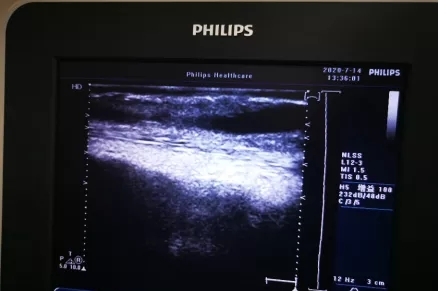

一般在穿刺前应该充分评估内瘘的震颤、杂音以及血管的弹性、质地。如有异常,不要盲目穿刺,避免内瘘失功。如果内瘘功能正常,穿刺后穿刺针内出现细条红色血栓,有可能是穿刺部位皮下有血栓,这个时候最好使用超声评估内瘘功能;必要时可以引导下穿刺内瘘,或重新评估穿刺点。还有种少见的情况是患者内瘘血管近心端有狭窄,导致穿刺段血管继发附壁血栓形成,有效管腔变窄、穿刺困难、血流不畅、血栓形成等。

自体内瘘附壁血栓▲